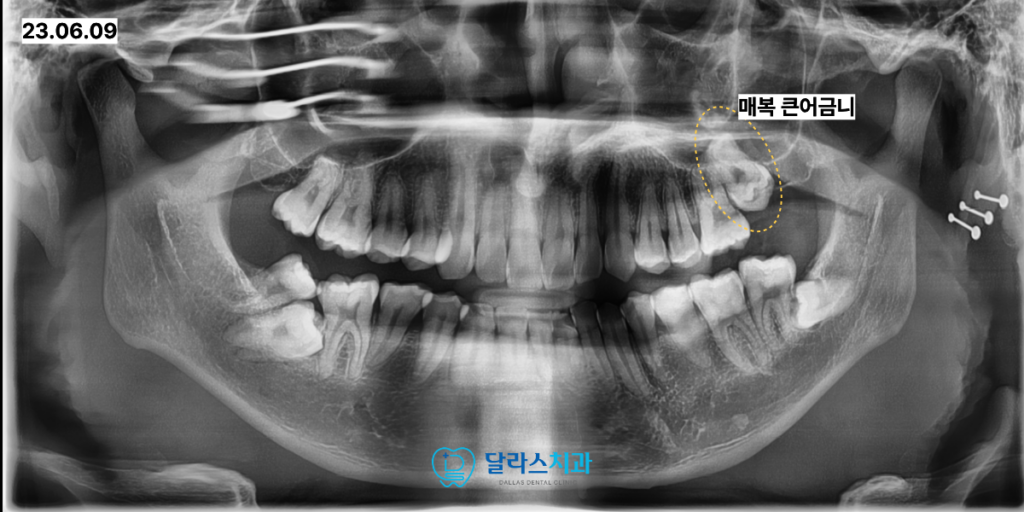

그 다음으로는 상악 좌측 큰어금니 역시 매복된 상태로 관찰되었습니다.

이 부위의 CT촬영을 동반한 정밀 분석 결과 치아를 아래로 견인하여 내려오게 하는 것이

현실적으로 매우 어렵고 성공률이 낮다는 판단이 내려졌습니다.

이에 따라 무리한 견인을 시도하기보다는 해당 치아를 발치한 후

부족한 뼈를 채워주는 골이식 술식을 병행하였습니다.

상악동 거상술을 함께 시행하여 임플란트가 식립될 충분한 공간을 확보하였고

최종적으로 임플란트를 식립하여 저작 기능을 회복해 드렸습니다.